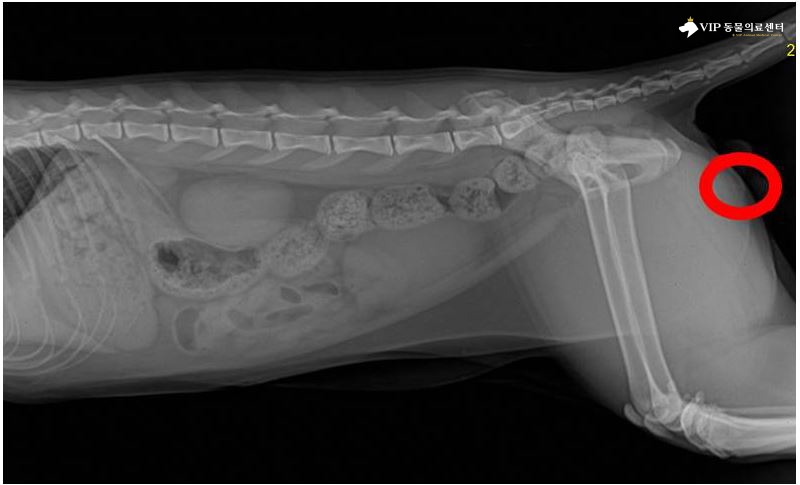

고양이 복부 방사선검사 촬영 시 요도 끝부분에 슬러지가 막고 있는 음영이 확인

조금 더 자세히 살펴보니, 초음파 검사 상 방광안에 슬러지가 매우 많이 차 있는 모습을 확인되며, 외관 상 흔들어서 초음파 상으로 봤을 때 방광 안이 매우 불순물로 가득차 있었습니다.

또한 방광염으로 인해 방광벽도 두꺼워져있으며, 상태가 불균일한 것이 확인되었습니다.